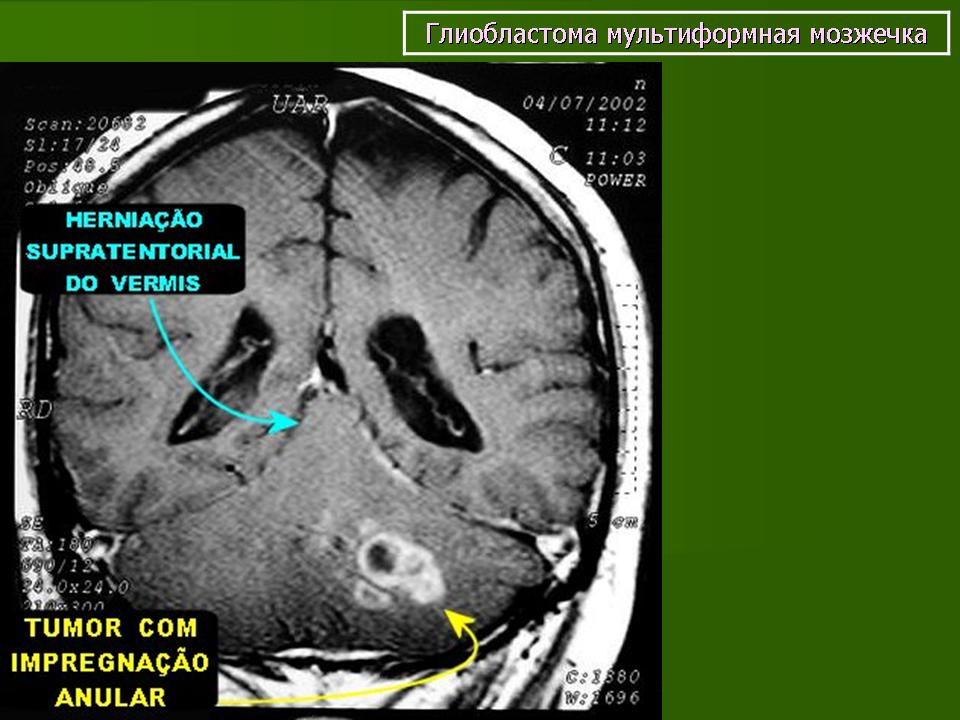

Глиобластома мультиформная